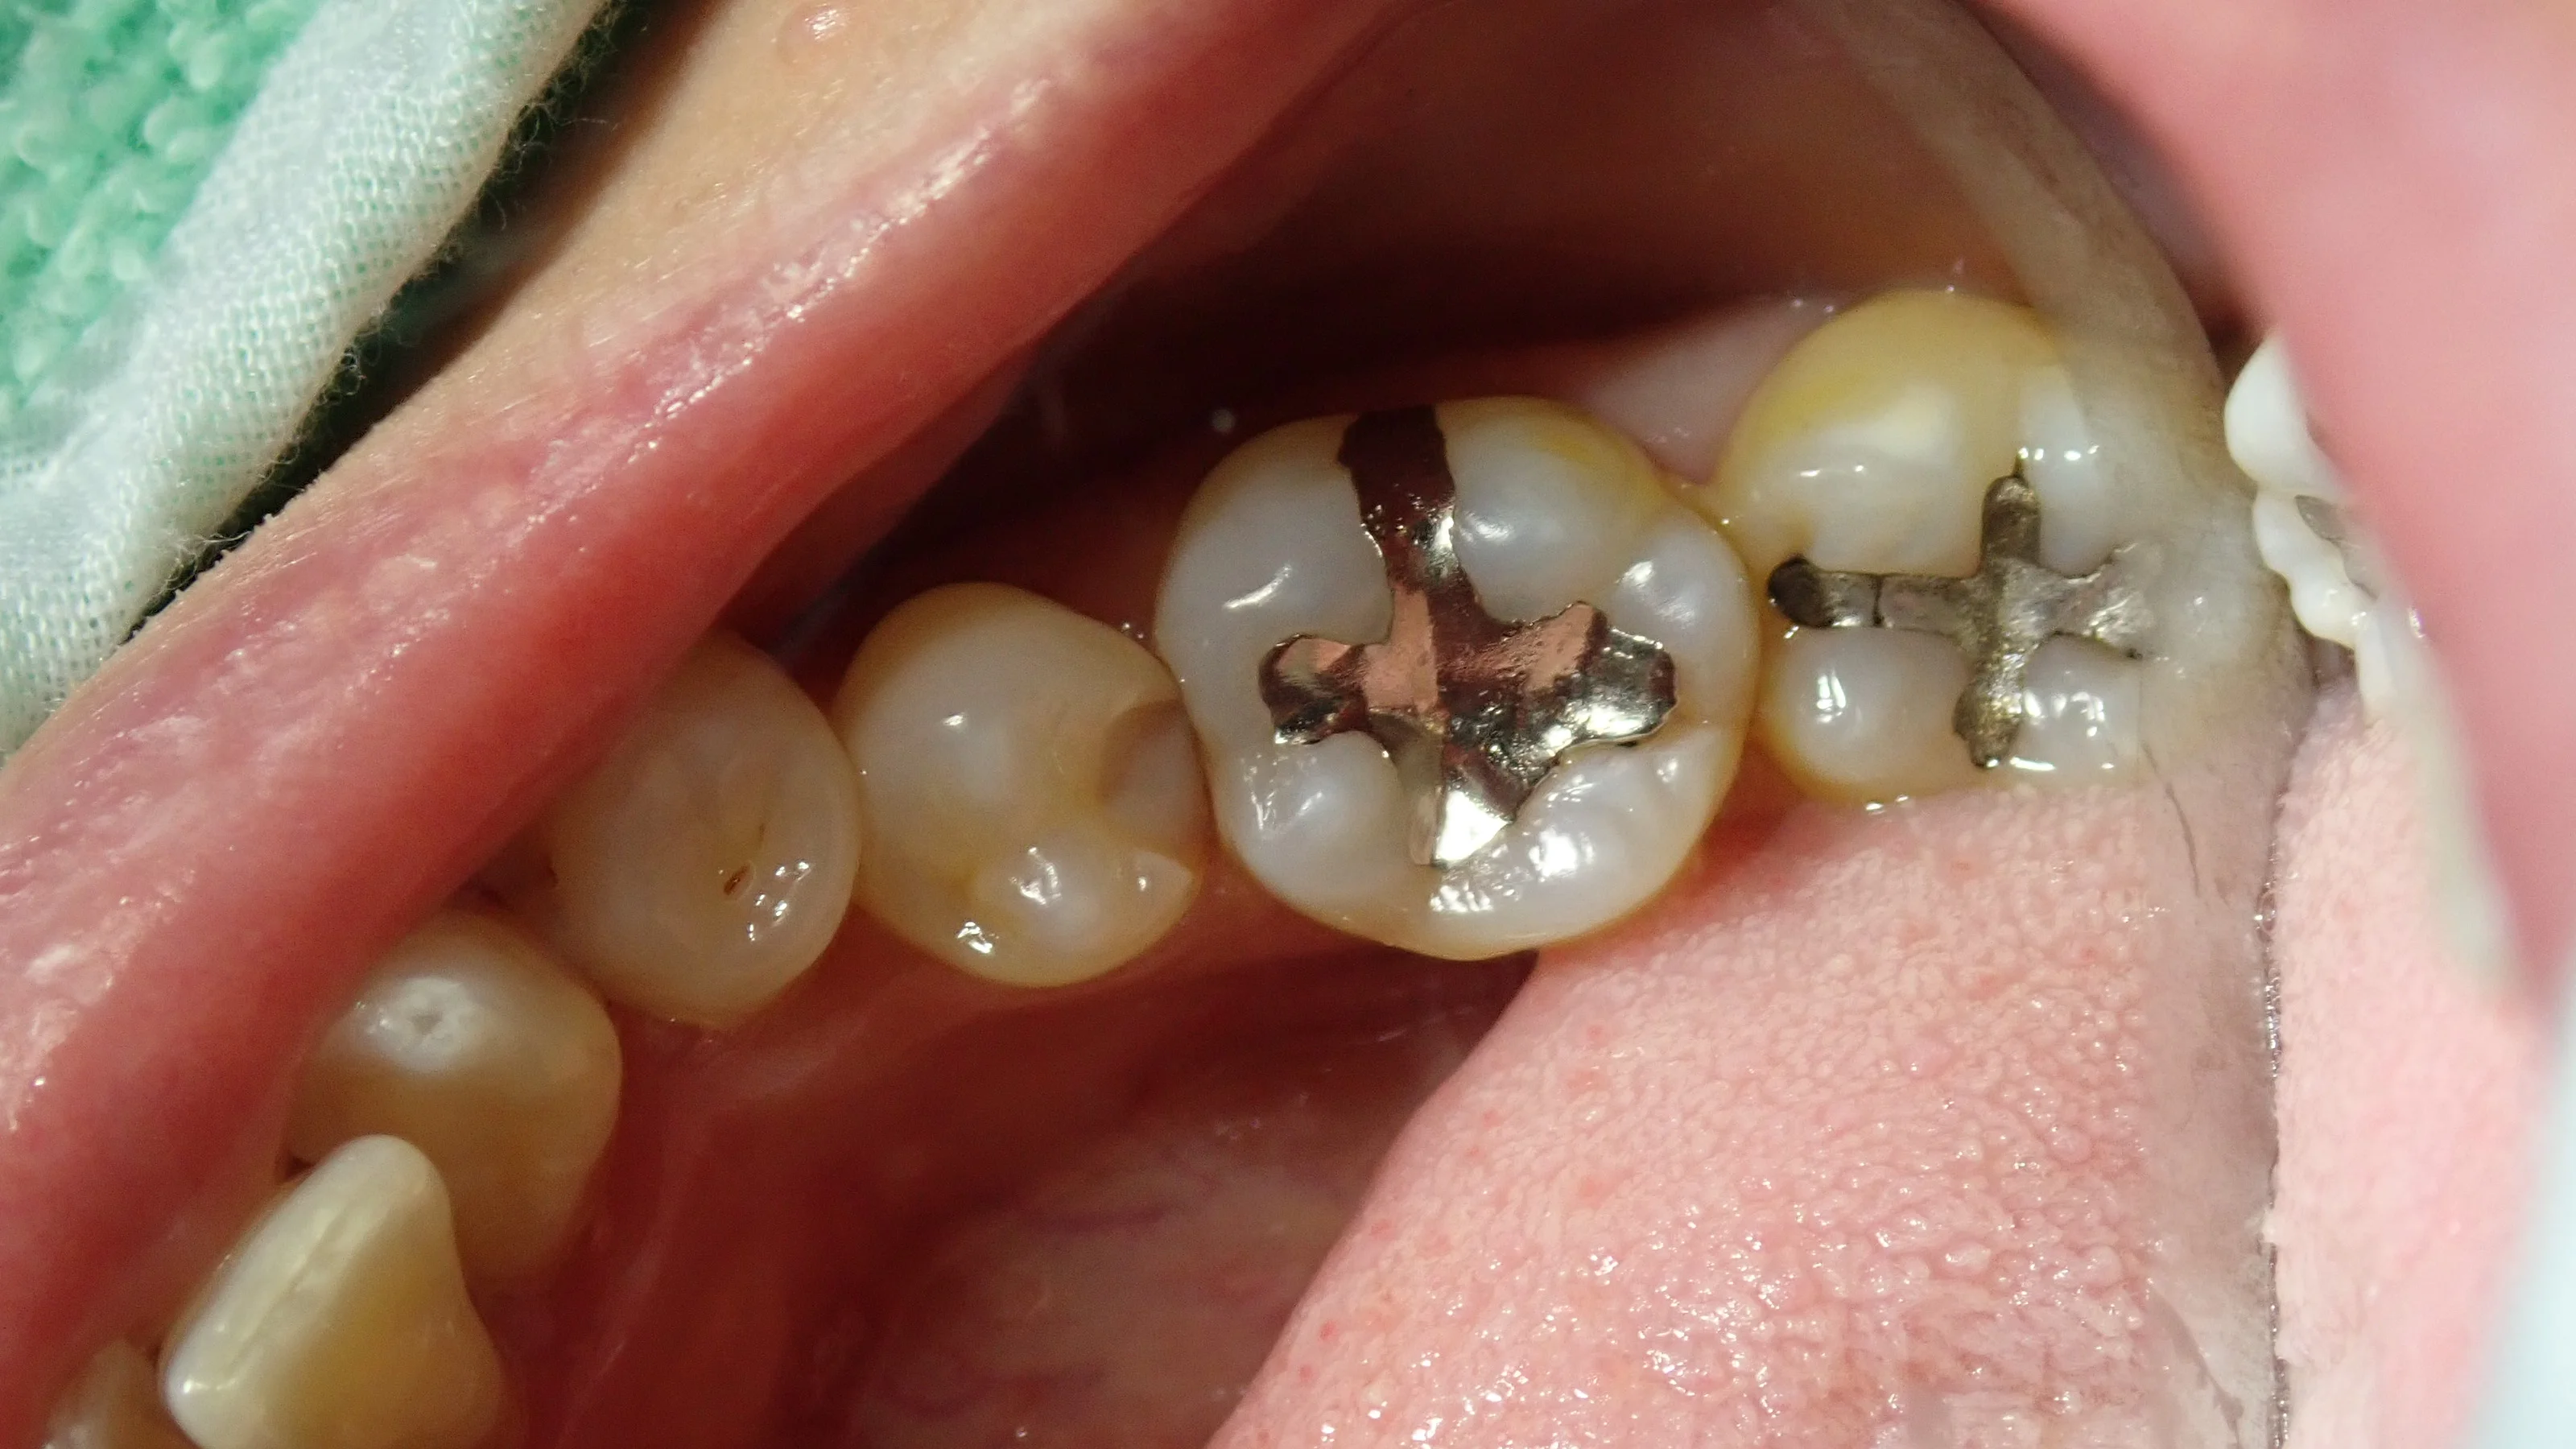

そして、こちらが虫歯を取りきった状態。

歯の色が随分と綺麗になっているのが分かるかと思います。

歯との間に虫歯があったので、そちらも一緒に除去しました。